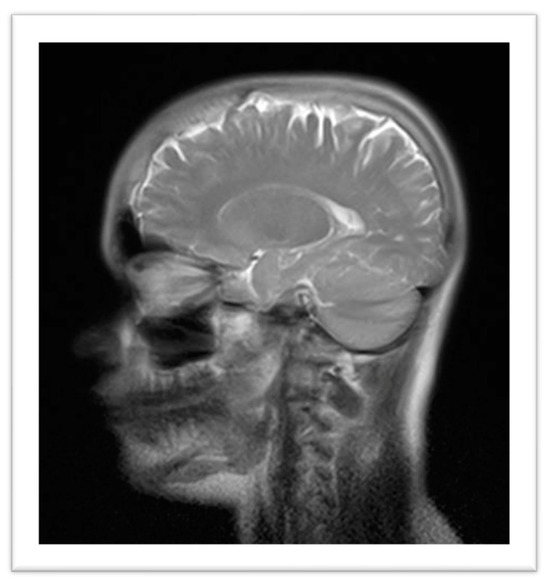

Imaging studies included a Brain Magnetic Resonance Imaging (MRI), which revealed calcification in the anterior aspect of the falx cerebri, hyperostosis of the inner calvaria table in the frontotemporoparietal regions, and asymmetry of the petrous apices, with the right side showing an area of T2 hyperintensity, without expansive effect, contrast enhancement, or diffusion restriction, potentially indicative of a mucocele or effusion (Figure 3). Radiographs of the pelvis, lower limbs, knees, and ankles showed bilateral cortical thickening of the diaphysis of long bones with areas of apparent bilateral and symmetrical hyperostosis (mid/distal femur diaphysis, proximal and distal tibia and fibula), with no significant difference in limb length (Figure 4).

Figure 3. Brain Magnetic Resonance Imaging: calcification in the anterior aspect of the falx cerebri, hyperostosis of the inner calvaria table in the frontotemporoparietal regions, and asymmetry of the petrous apices.